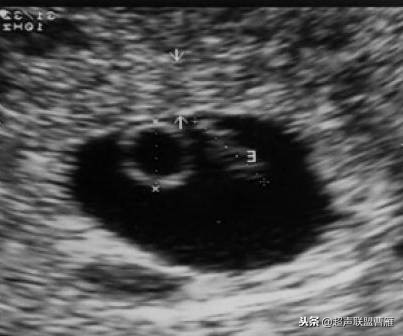

一个孕囊有两个卵黄囊,单卵双胎。

两个孕囊各有一个卵黄囊,双卵双胎,HCG应该更高。